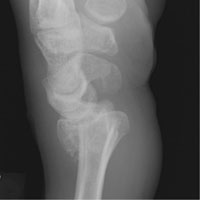

- Click on the image for a larger versionBLateral radiograph of the wrist. This shows the typical appearance of Colles fracture with dorsal tilt of the distal radial fracture fragment.